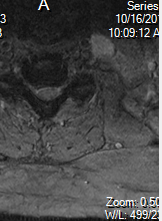

C4-C5: Small to moderate posterior disc osteophyte complex with right paracentral and lateral recess component resulting in moderate spinal canal narrowing and deformation of the ventral cord. There is moderate to severe right and mild left neural

foraminal narrowing.

C5-C6: Moderate posterior disc osteophyte complex and bilateral facet arthropathy resulting in severe spinal canal narrowing. There is severe right and moderate to severe left neural foraminal narrowing.

C6-C7: Moderate posterior disc osteophyte complex and bilateral facet arthropathy resulting in moderate to severe spinal canal narrowing. There is moderate to severe right and moderate left neural foraminal narrowing.

There is CSF on both sides in the sagittal cuts and there is no contouring of the cord at all.

What level is your axial slice? C5-6? And yeah if he doesn't have any long track signs I wouldn't get too excited. In fact I see cervical spines like this all time here at the VA and the surgeon almost always wants to watch them. Then again he's not getting paid per surgery like your guy 😉

No signal in cord..not myelopathic..doesn't need decompression yet. I would treat with pt, nsaids, low volume cesi. Obvi discuss how cervical spondylitic myelopathy can present with stepwise neurological decline...

If the AP diameter is 9mm, it cannot be severe stenosis unless the cord itself is enlarged at that level- it does not appear to be. I agree with others that there is not severe central stenosis, and that this is an over-read or misread by the radiologist. The misinterpretation by the radiologist accompanied by some symptoms that may be attributable to foraminal stenosis may be prompting the surgeon to move (inappropriately) directly to surgery. However, there are not any other significant medical or alternative medicine techniques that will undo foraminal stenosis, so it is somewhat of a judgement call about when to pull the trigger.